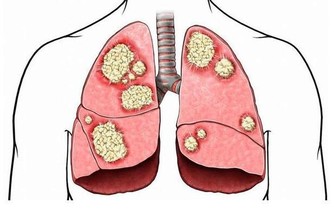

尤其是老年人,午睡時間超過90分鐘,就會增加心腦血管疾病的發生率。對於沒有午睡習慣的人,以白天自我感受的清晰度為主,只要不覺得困倦、疲勞,完全可以不需要午睡。